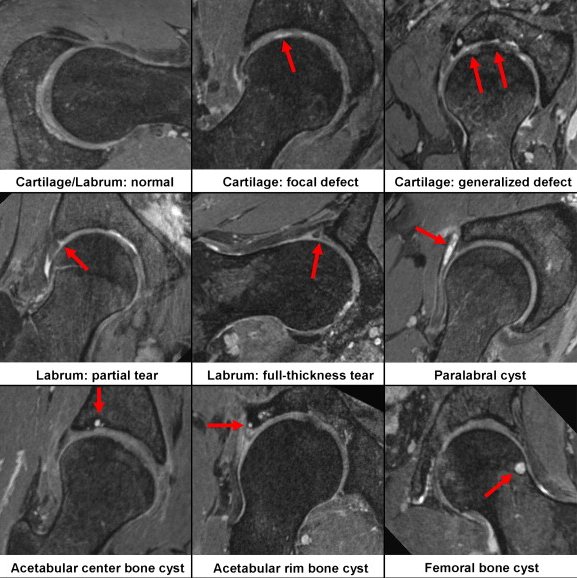

Repeated abnormal contact between the neck of the femur and the rim of the acetabulum is associated with wear in the hip. This is visible as damage to the labrum of the hip, wear of the adjacent chondral surfaces and occasional para-labral cysts (fluid "bubbles").

Again it is important to note that these "abnormalities" and this type of wear is commonly found in people with no symptoms.